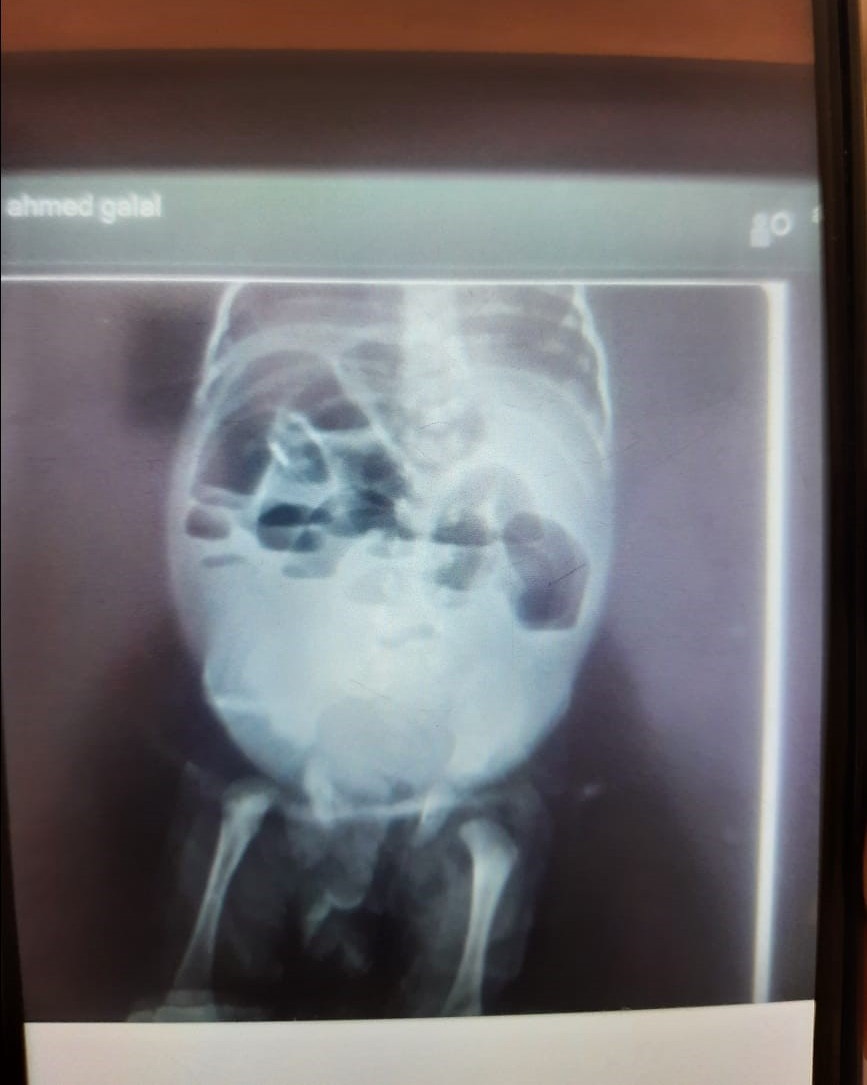

Plain X-ray abdomen standing showed severe gaseous distension, multiple sharp air fluid levels, and absence of gas distribution in the lower abdomen. The cardiac shadow was obscured (Figure 1).

Figure 1: Plain X-ray abdomen showing multiple sharp air fluid levels.